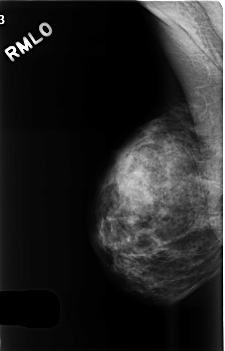

C_0509_1.RIGHT_MLO

RIGHT_MLO LINES 4552 PIXELS_PER_LINE 2920 BITS_PER_PIXEL 12 RESOLUTION 50 NON_OVERLAY